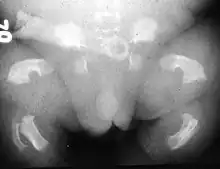

| Radiogram of a baby born with thanatophoric dwarfism | |